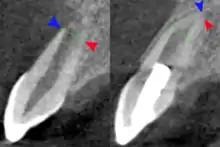

The secondary therapeutic goal of regenerative endodontic procedures is continued root development. A study has shown that teeth treated with revascularization showed a significantly greater percentage increase in root length compared with teeth treated by either mineral trioxide aggregate or calcium hydroxide apexification. Regenerative procedures promoted a decrease in apical diameter (apical closure). Root development allows the increase of the resistance to fracture and improve the tooth survival rate.[46]

Radiograph images, before and after the procedure are used to evaluate the outcome of the treatment. The patients are scheduled to follow up at 3, 6, 9, and 12 months after the completion of therapy. The tooth is accessed for different aspects such as pain, swelling, sinus tract, mobility, tooth discoloration, and the occlusion relationship. At the 12-month follow-up, CBCT images are taken to analyze the root development, in specific to access for the disappearance of apical radiolucency, increase of root length or a decrease of the apical foramen, or both.[51]